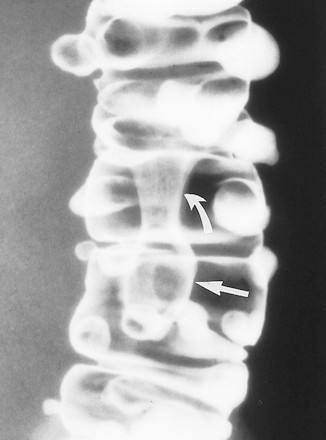

Ung thư biểu mô hình khuyên hay phát triển ở vùng sigma nhất nhưng cũng có thể thấy ở đại tràng xuống, đại tràng ngang, và đại tràng lên. Trái lại, chúng không xảy ra ở manh tràng và trực tràng do khẩu kính của các đoạn đó lớn. Các tổn thương hình khuyên biểu hiện trên phim cản quang baryt bằng hẹp chu vi lòng ruột, với sự phá hủy niêm mạc, với các bờ nhô lên như dải đá ngầm (Hình 11, 12). Chủ yếu phải quan sát các quai ruột tách nhau, nếu quai ruột chồng nhau có thể không quan sát thấy tổn thương (Hình 12).

Hình 11. Hình cản quang kép khu trú, bệnh nhân nằm ngửa phát hiện hai ung thư biểu mô tuyến đồng thời. Khối ung thư biểu mô hình khuyên ở đoạn cuối đại tràng ngang đặc trưng bởi sự phá hủy niêm mạc và các bờ nhô lên hình đá ngầm (mũi tên trắng, thẳng). Khối ung thư biểu mô tuyến thứ hai dạng polyp (mũi tên đen) nằm ở đoạn đầu đại tràng ngang. Bệnh nhân này cũng có một polyp tuyến (mũi tên trắng, cong) ở sát bờ ngoài tổn thương hình khuyên.

Hình 12. Hình cản quang kép cho thấy tầm quan trọng của tư thế để bộ lộ tổn thương hình khuyên. (a) Hình nằm ngửa ban đầu cho thấy các túi thừa, nhưng góc gan không quan sát rõ. (b) Hình chếch sau trái cho thấy rõ tổn thương hình khuyên ở đại tràng góc gan, không thấy trên phim (a) ban đầu.